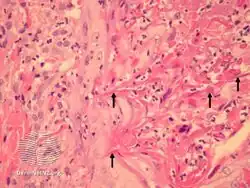

Perforating folliculitis

Perforating folliculitis is a skin condition in humans characterized by discrete follicular keratotic eruptions involving mainly the hairy parts of the extremities.[1]: 539–540